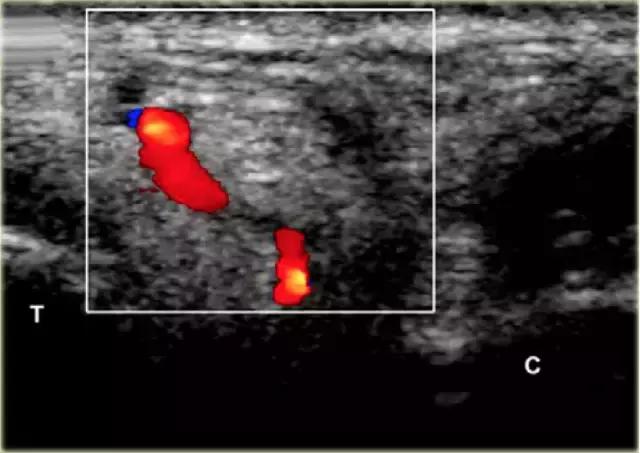

超声引导的跗骨窦的注射在右手侧与外侧入路。探头保持在冠状倾斜平面中。针沿着探头的长轴引入。

使用超声波可以容易地观察窦性骨壁。患者转向对侧,将待治疗的足以其内侧表面靠在桌面上,脚的外侧位于最上面。探头保持在关于脚的冠状平面中。

在跗骨窦被识别为跟骨的前处理和距骨颈之间的三角空间。针(箭头)的前端的锥形跗骨窦,这是由距骨(T)和跟骨(C)的边界内可以看到。

根据炎症的程度,可能存在空间的充血,并且可能存在中间血管可见,这是人们希望避免的。但是这又是比较容易的,特别是彩色多普勒。